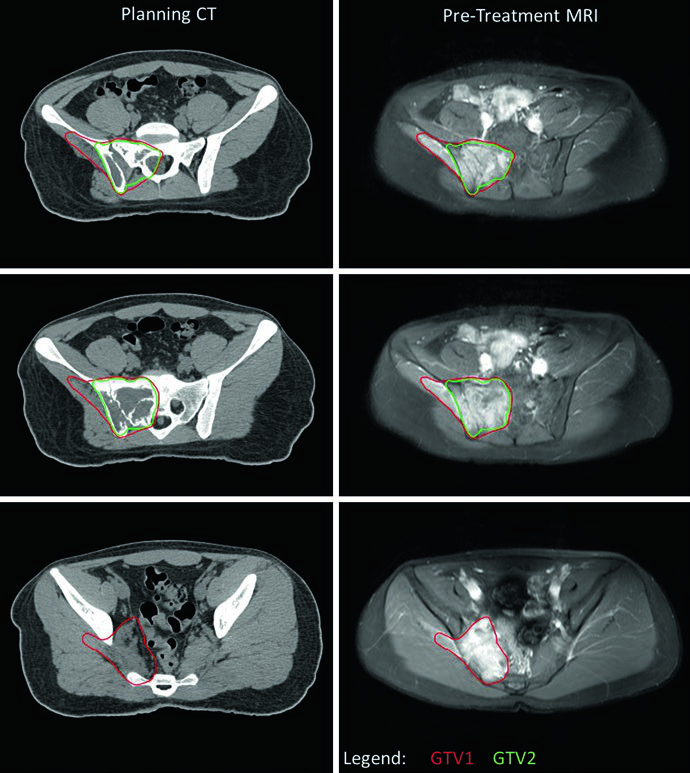

O caso de RMS alveolar (fusão-positivo) de extremidade superior com adenopatia axilar bilateral destaca a abordagem quando há metástases nodais regionais. Toda a bacia axilar direita foi contornada como GTV para garantir cobertura completa, dado o envolvimento extenso identificado no PET. O sítio primário na mão respondeu minimamente e recebeu dose única de 50,4 Gy; a bacia axilar, apesar de resposta parcial, também recebeu 50,4 Gy em nível único pela difusividade do envolvimento. Não foram identificados sítios de doença em trânsito entre mão e axila, e portanto o braço intermediário não foi tratado.